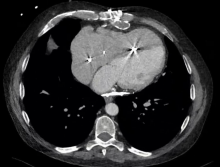

Preoperative transthoracic echocardiography and cardiac magnetic resonance imaging (MRI) demonstrated a thickened pericardium. Imaging also indicated an increased mitral E/A ratio after atrial contraction, high (≥9 cm/sec) mitral medial annular early diastolic velocity, and paradoxical septal motion. These results were consistent with cases of constrictive pericarditis and decreased biventricular systolic function (LVEF 45%) with severe tricuspid regurgitation. Right heart catheterization revealed equalization of diastolic filling pressures, moderate pulmonary hypertension, pulmonary capillary wedge pressure of 28 mmHg, and a cardiac index of 1.8 L/min/m2. Next, a chest computed tomography demonstrated a focal fluid collection in the anterior mediastinum, with circumferential calcification and significant compression of the right ventricle. There was a similar collection along the surface of the diaphragm.